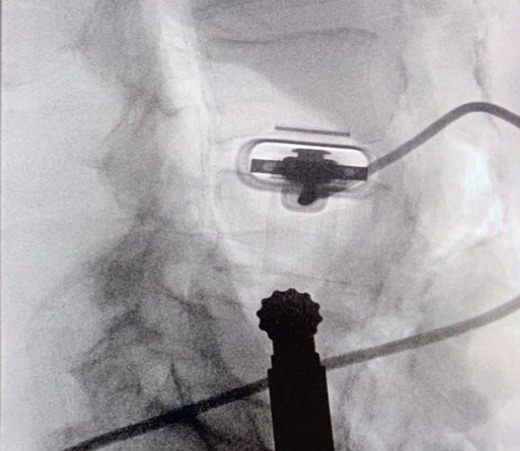

Several devices have been introduced for use in navigation of the lumbar plexus to combat these complications. This includes the use of pre-operative images registered with fluoroscopy, O-arm technology to develop 3D images, and intraoperative MRI (Figure 2). However, these modalities are lacking in their ability to accommodate dynamic anatomy during surgery. An alternative imaging technique involves indirect location of neural structures using directional electromyography (EMG) monitoring (Neuro-Vision, NuVasive, San Diego, CA). This technology is best used for identification of nerves in the path of the lateral approach (specifically around the psoas; Tohmeh, Rodgers, and Peterson 2011; Ebata, Ohba, and Haro 2019).

Currently, no effective options for real-time intraoperative soft tissue imaging for spine procedures exist. Commonly used X-ray and fluoroscopic technology do not allow for adequate visualization of soft tissue structures. There are currently several modalities utilized for soft-tissue localization in spine surgery. However, these too present with significant limitations. Preoperative MRIs are registered to images taken throughout the procedure to create a “merged” image, but while such techniques may be somewhat helpful as a reference, it is time consuming and is not always representative of the true anatomical layout, as tissue shifts during surgery. Intraoperative MRI was also at one point suggested as an option, and although it offers high resolution of important neural and muscular tissue, it offers poor differentiation of bone and is unlikely to be used during the procedure (Woodard et al. 2001). Most recently, use of intraoperative CT was shown to provide accurate navigation in LLIF procedures; however, its ability to help identify vital neurological structures is yet to be established (Joseph et al. 2016).